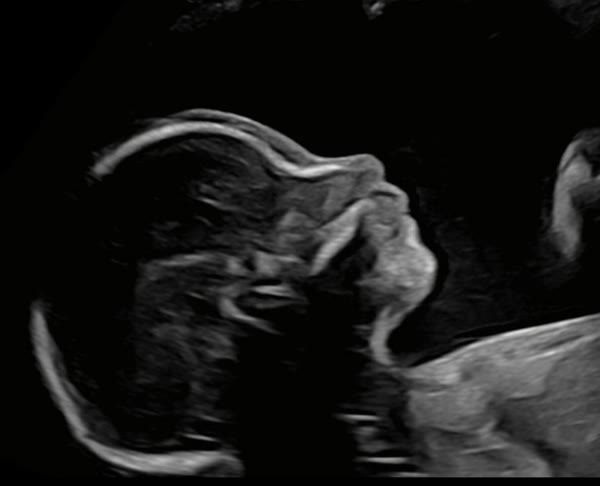

Des échographies adaptées à chaque situation clinique, réalisées directement au cabinet.

Échographies de datation, du premier, deuxième et troisième trimestre.